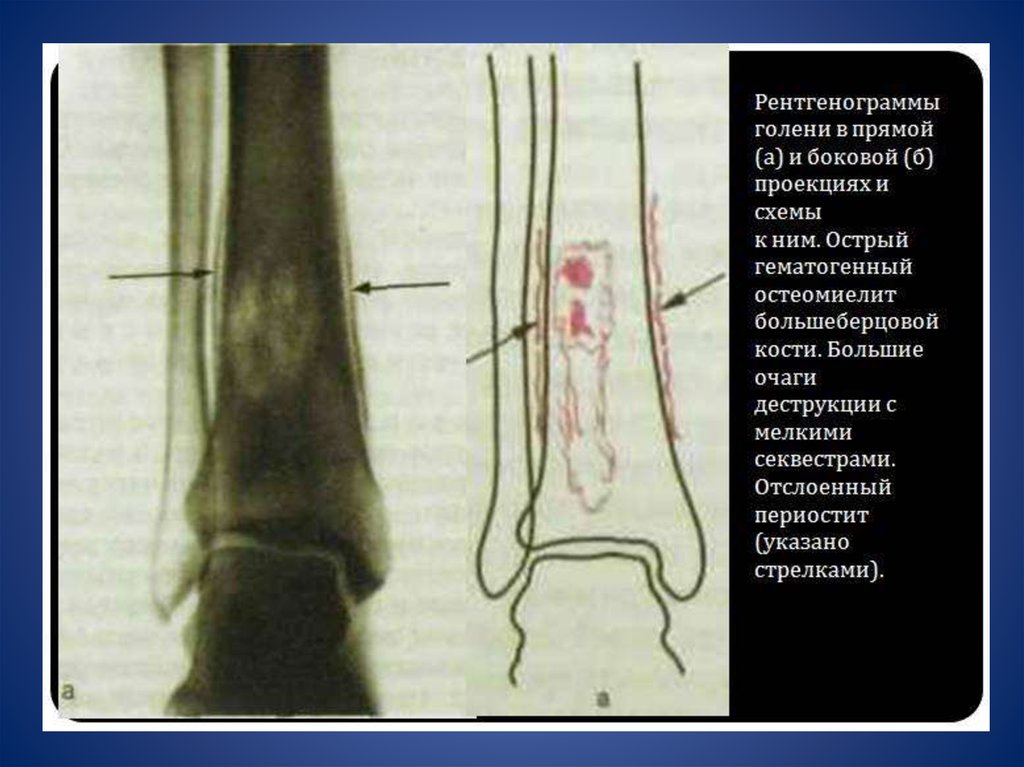

Рентгенологические симптомы

хронического остеомиелита.

2.

рентгенологической диагностики. Впоследствии методика